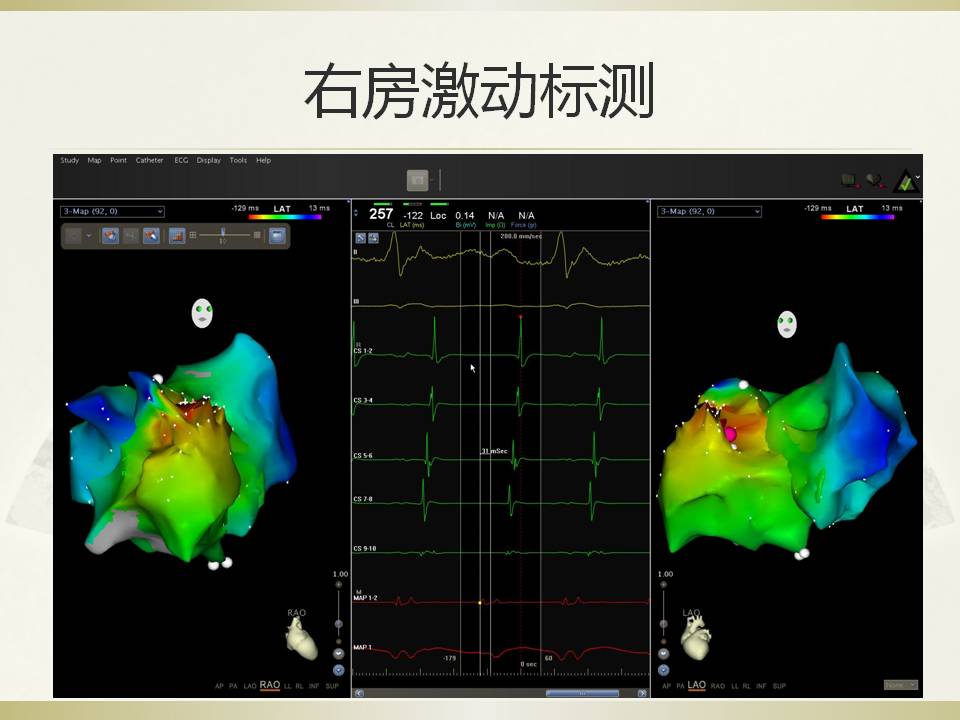

房速1例的射频消融

雷森 何泉